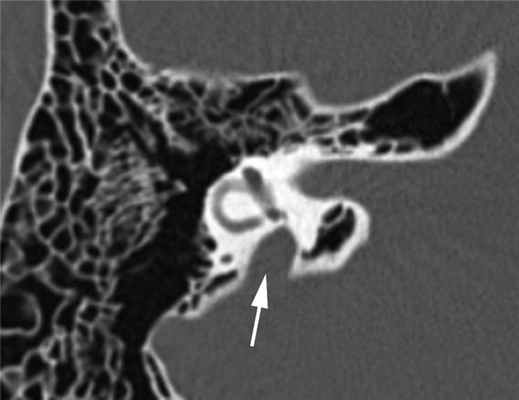

Диагностика. СРВП часто мимикрирует заболевания среднего уха. Известно, что аномальное соединение внутреннего уха с подоболочечным пространством головного мозга, также как и «третье окно» лабиринта, может давать костно-воздушный разрыв на аудиограмме, более выраженный на низких частотах. Это явление описано в англоязычной литературе как интралабиринтная кондуктивная тугоухость, «псевдокондуктивная» тугоухость или «ложная» кондуктивная тугоухость [18]. Поэтому любое снижение слуха, характеризующееся нормальными тимпанограммами типа А, наличием акустических рефлексов и костно-воздушного интервала, более выраженного на низких частотах, должно вызывать подозрение на аномалию внутреннего уха. В таких случаях показано проведение высокоразрешающей мультиспиральной КТ височных костей, что позволит избежать эксплоративной тимпанотомии, проводимой ошибочно по поводу смешанной или кондуктивной тугоухости неясного генеза. На К.Т. данный синдром характеризуется расширением водопровода преддверия от 1,5 до 5—6 мм (рис. 2).

Рис. 2. Широкий водопровод преддверия (стрелка). Компьютерная томограмма правой височной кости в аксиальной проекции. Пациент А., 14 лет.